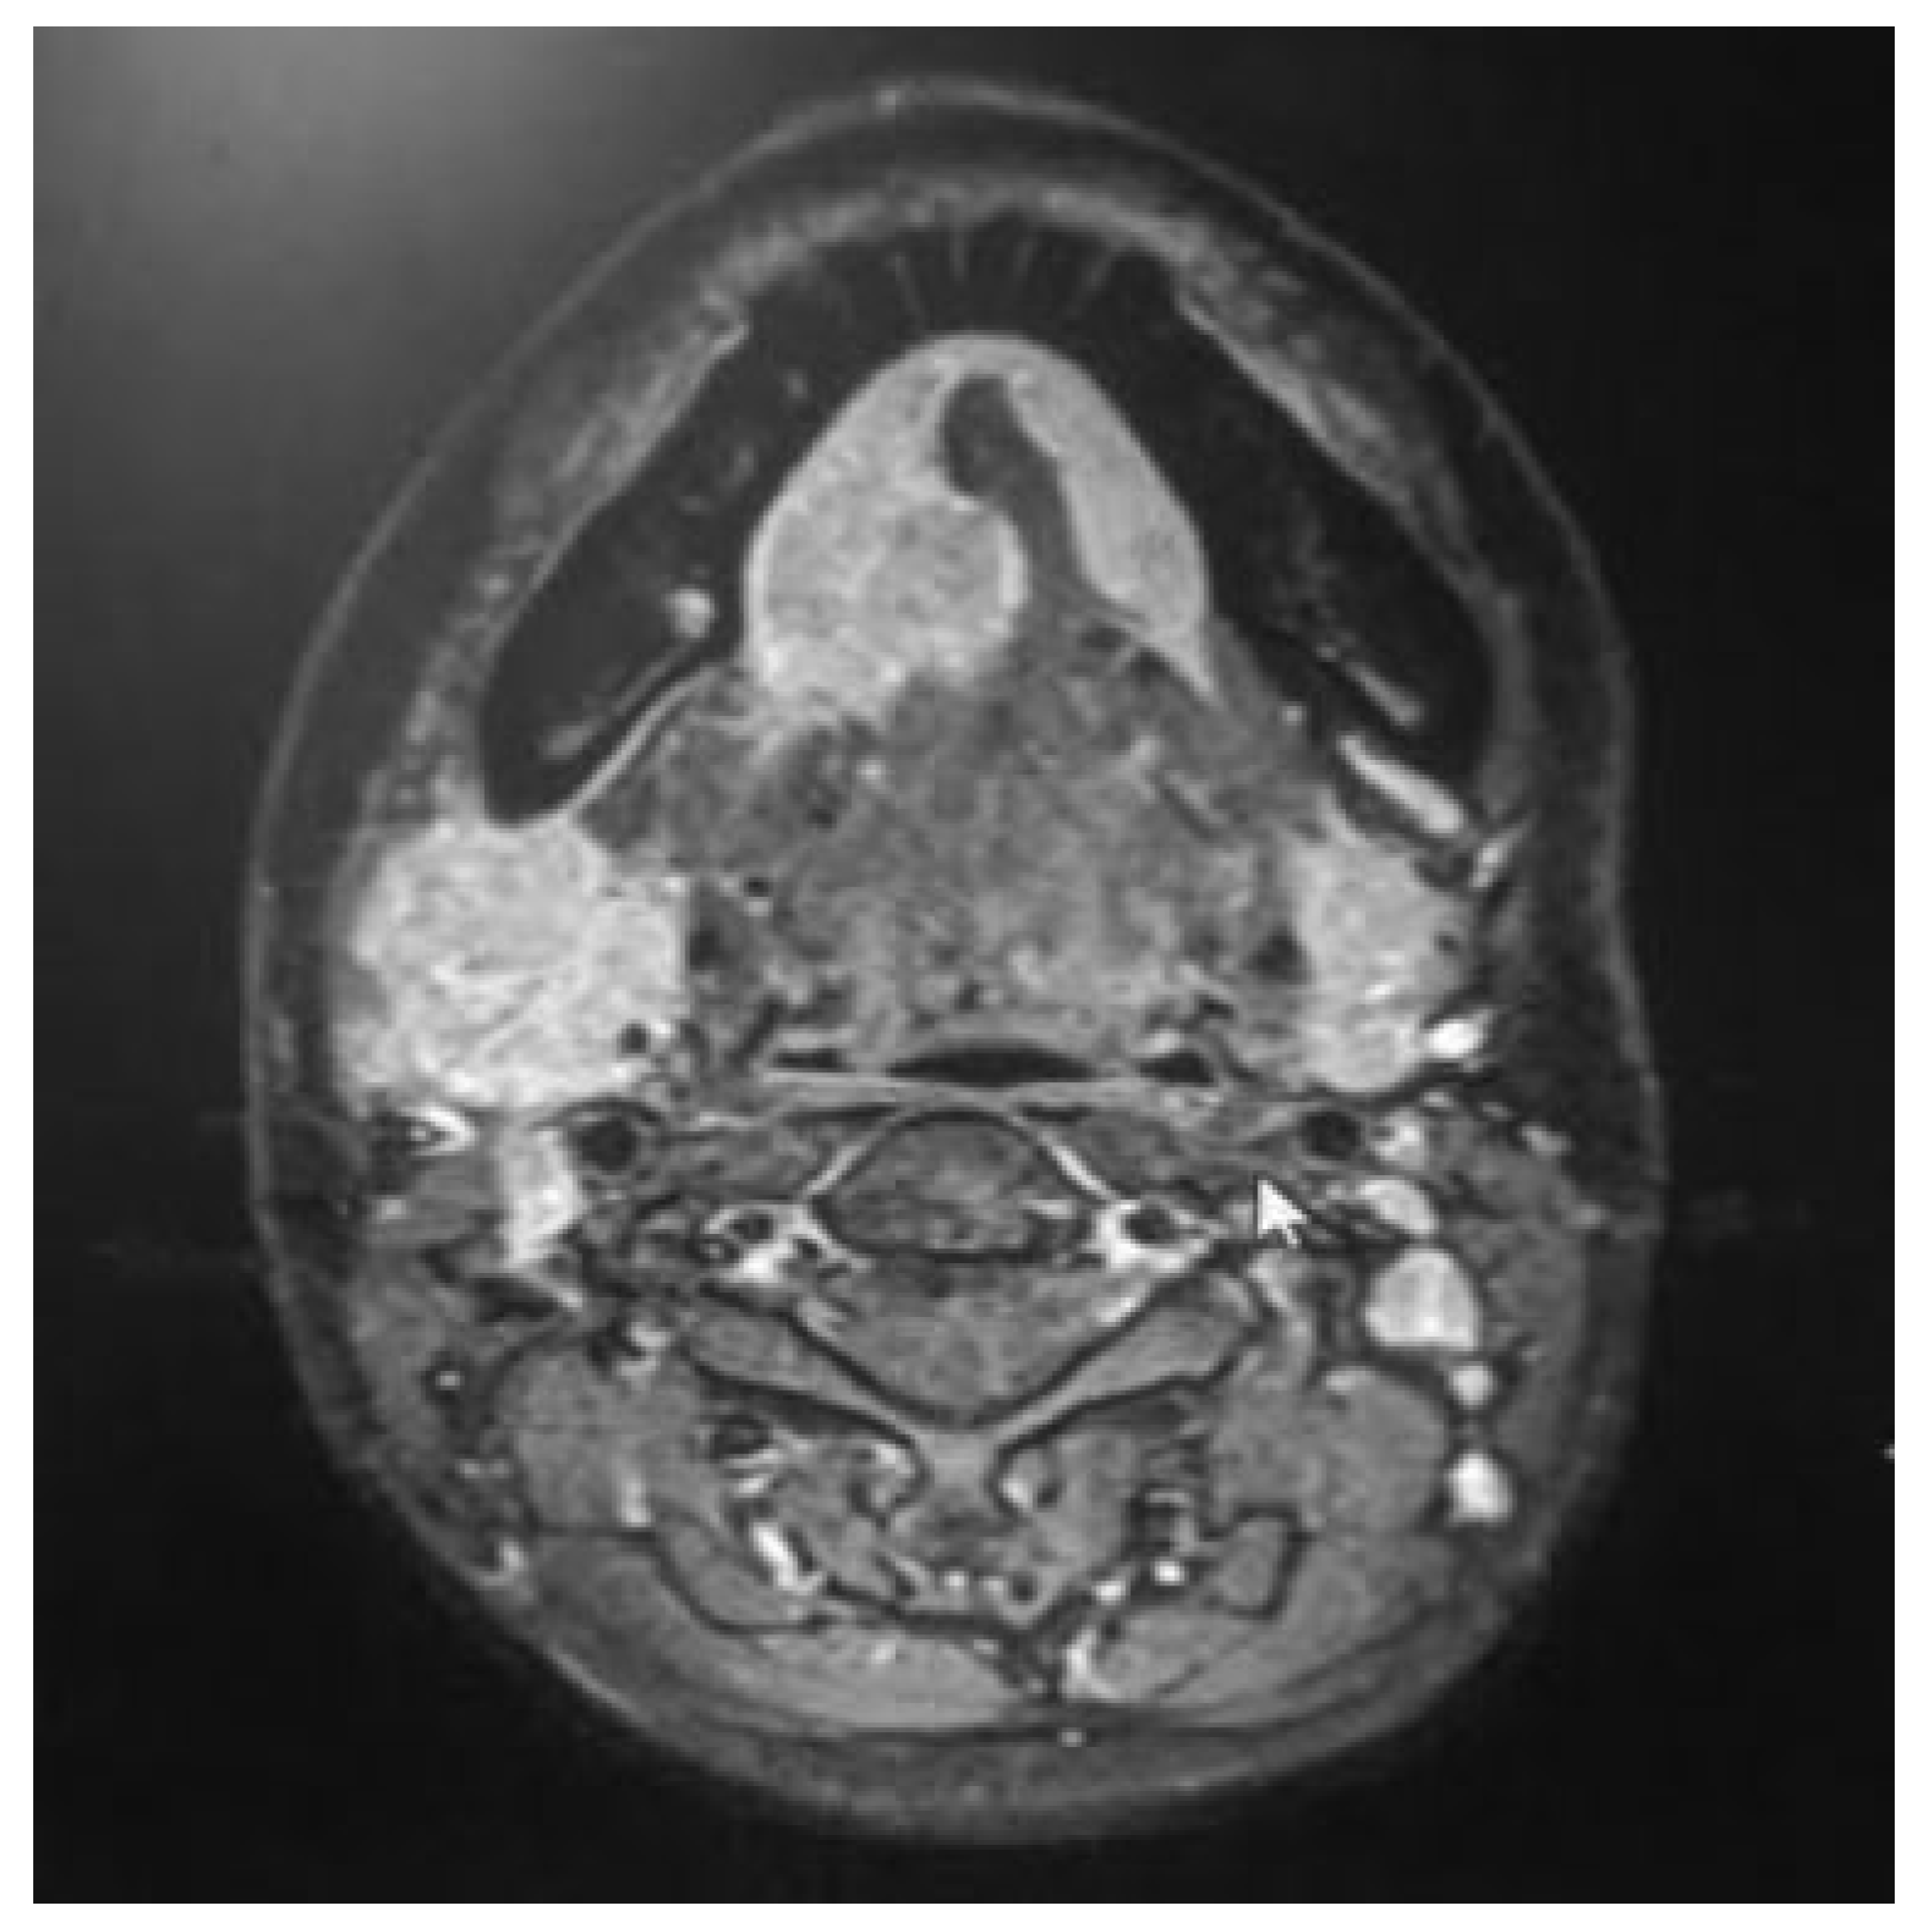

Contralateral Islanded Facial Artery Myomucosal Flap for the Reconstruction of Floor of the Mouth Defect

Shivanand, N.B.; Mohan, M.T.; Joseph, S.T. Contralateral Islanded Facial Artery Myomucosal Flap for the Reconstruction of Floor of the Mouth Defect. Craniomaxillofac. Trauma Reconstr. 2018, 11, 157-160. https://doi.org/10.1055/s-0037-1604071